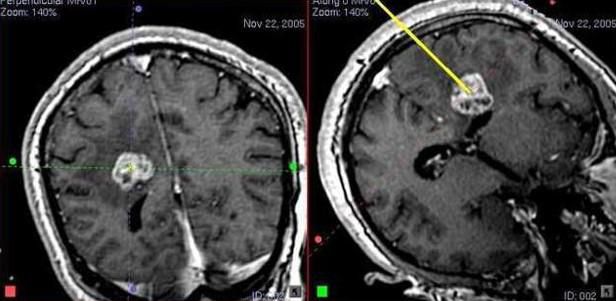

Іноді, при пухлинах, які явно неможливо видалити або при сумнівах в природі внутрішньомозкової пухлини, проводиться діагностична операція біопсія пухлини головного мозку. Це втручання полягає в тому, що через невеликий фрезевий отвір в кістках черепа спеціальний інструментарій підводиться до пухлинного вузла і береться зразок тканини пухлини для гістологічного і, або, гістохімічного дослідження.